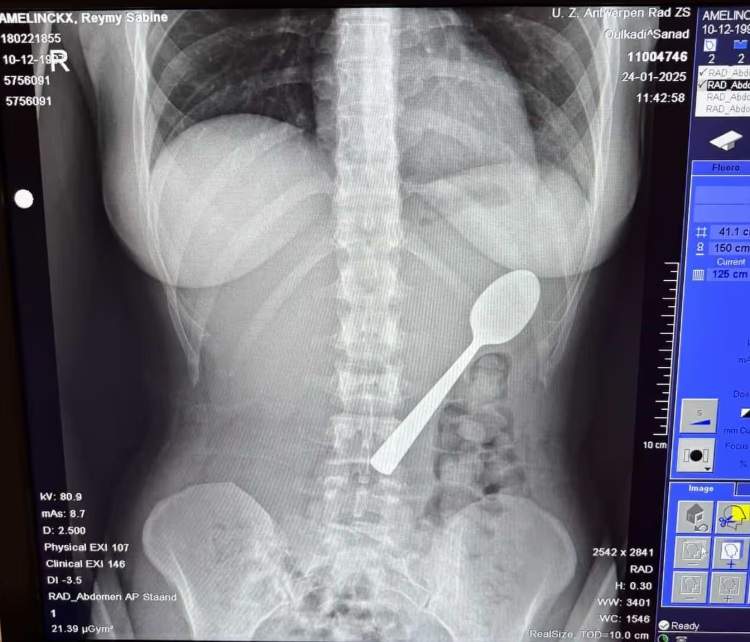

O femeie a înghițit o lingură de 17 cm în timp ce mânca iaurt

O femeie a înghițit o lingură de 17 cm în timp ce mânca iaurt. Cum a fost posibil